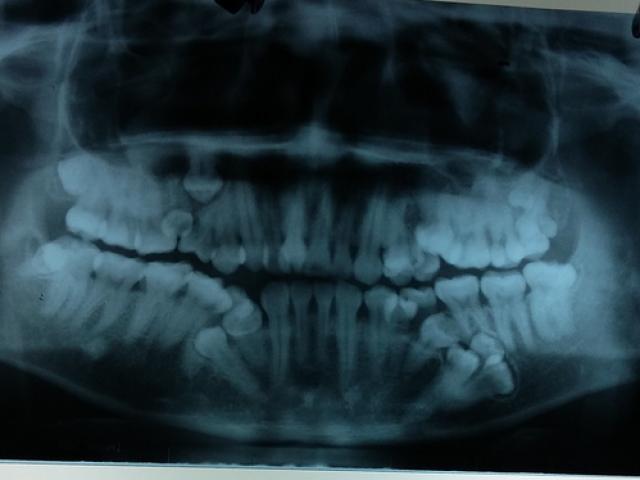

Theo Vietnamnet, khi tình hình ngày càng xấu đi, Fang đã quyết định đi gặp bác sĩ và vô cùng sốc khi biết có một chiếc răng dài khoảng 2,5 cm đang mọc ở dưới hốc mắt.

Cô được khuyên cần chuyển lên bệnh viện lớn hơn để phẫu thuật càng sớm càng tốt vì nếu chiếc răng tiếp tục mọc, về lâu dài nó sẽ hủy hoại đôi mắt của cô. Fang đã chọn một bệnh viện ở thành phố Trùng Khánh để thực hiện phẫu thuật.

Tại đây, bác sĩ Lin đã rạch một đường nhỏ trên mặt cô để lấy chiếc răng ra.

Bác sĩ Lin, người thực hiện phẫu thuật cho Fang cho biết chiếc răng mọc sai hướng của cô có thể do răng sữa rụng không kịp nên chiếc răng này không có chỗ để chồi ra và phải mọc ngược.

Theo Bệnh viện Đại học Cambridge, đây là hiện tượng răng bị nén chặt vào xương hàm nên không mọc qua lợi một cách bình thường.